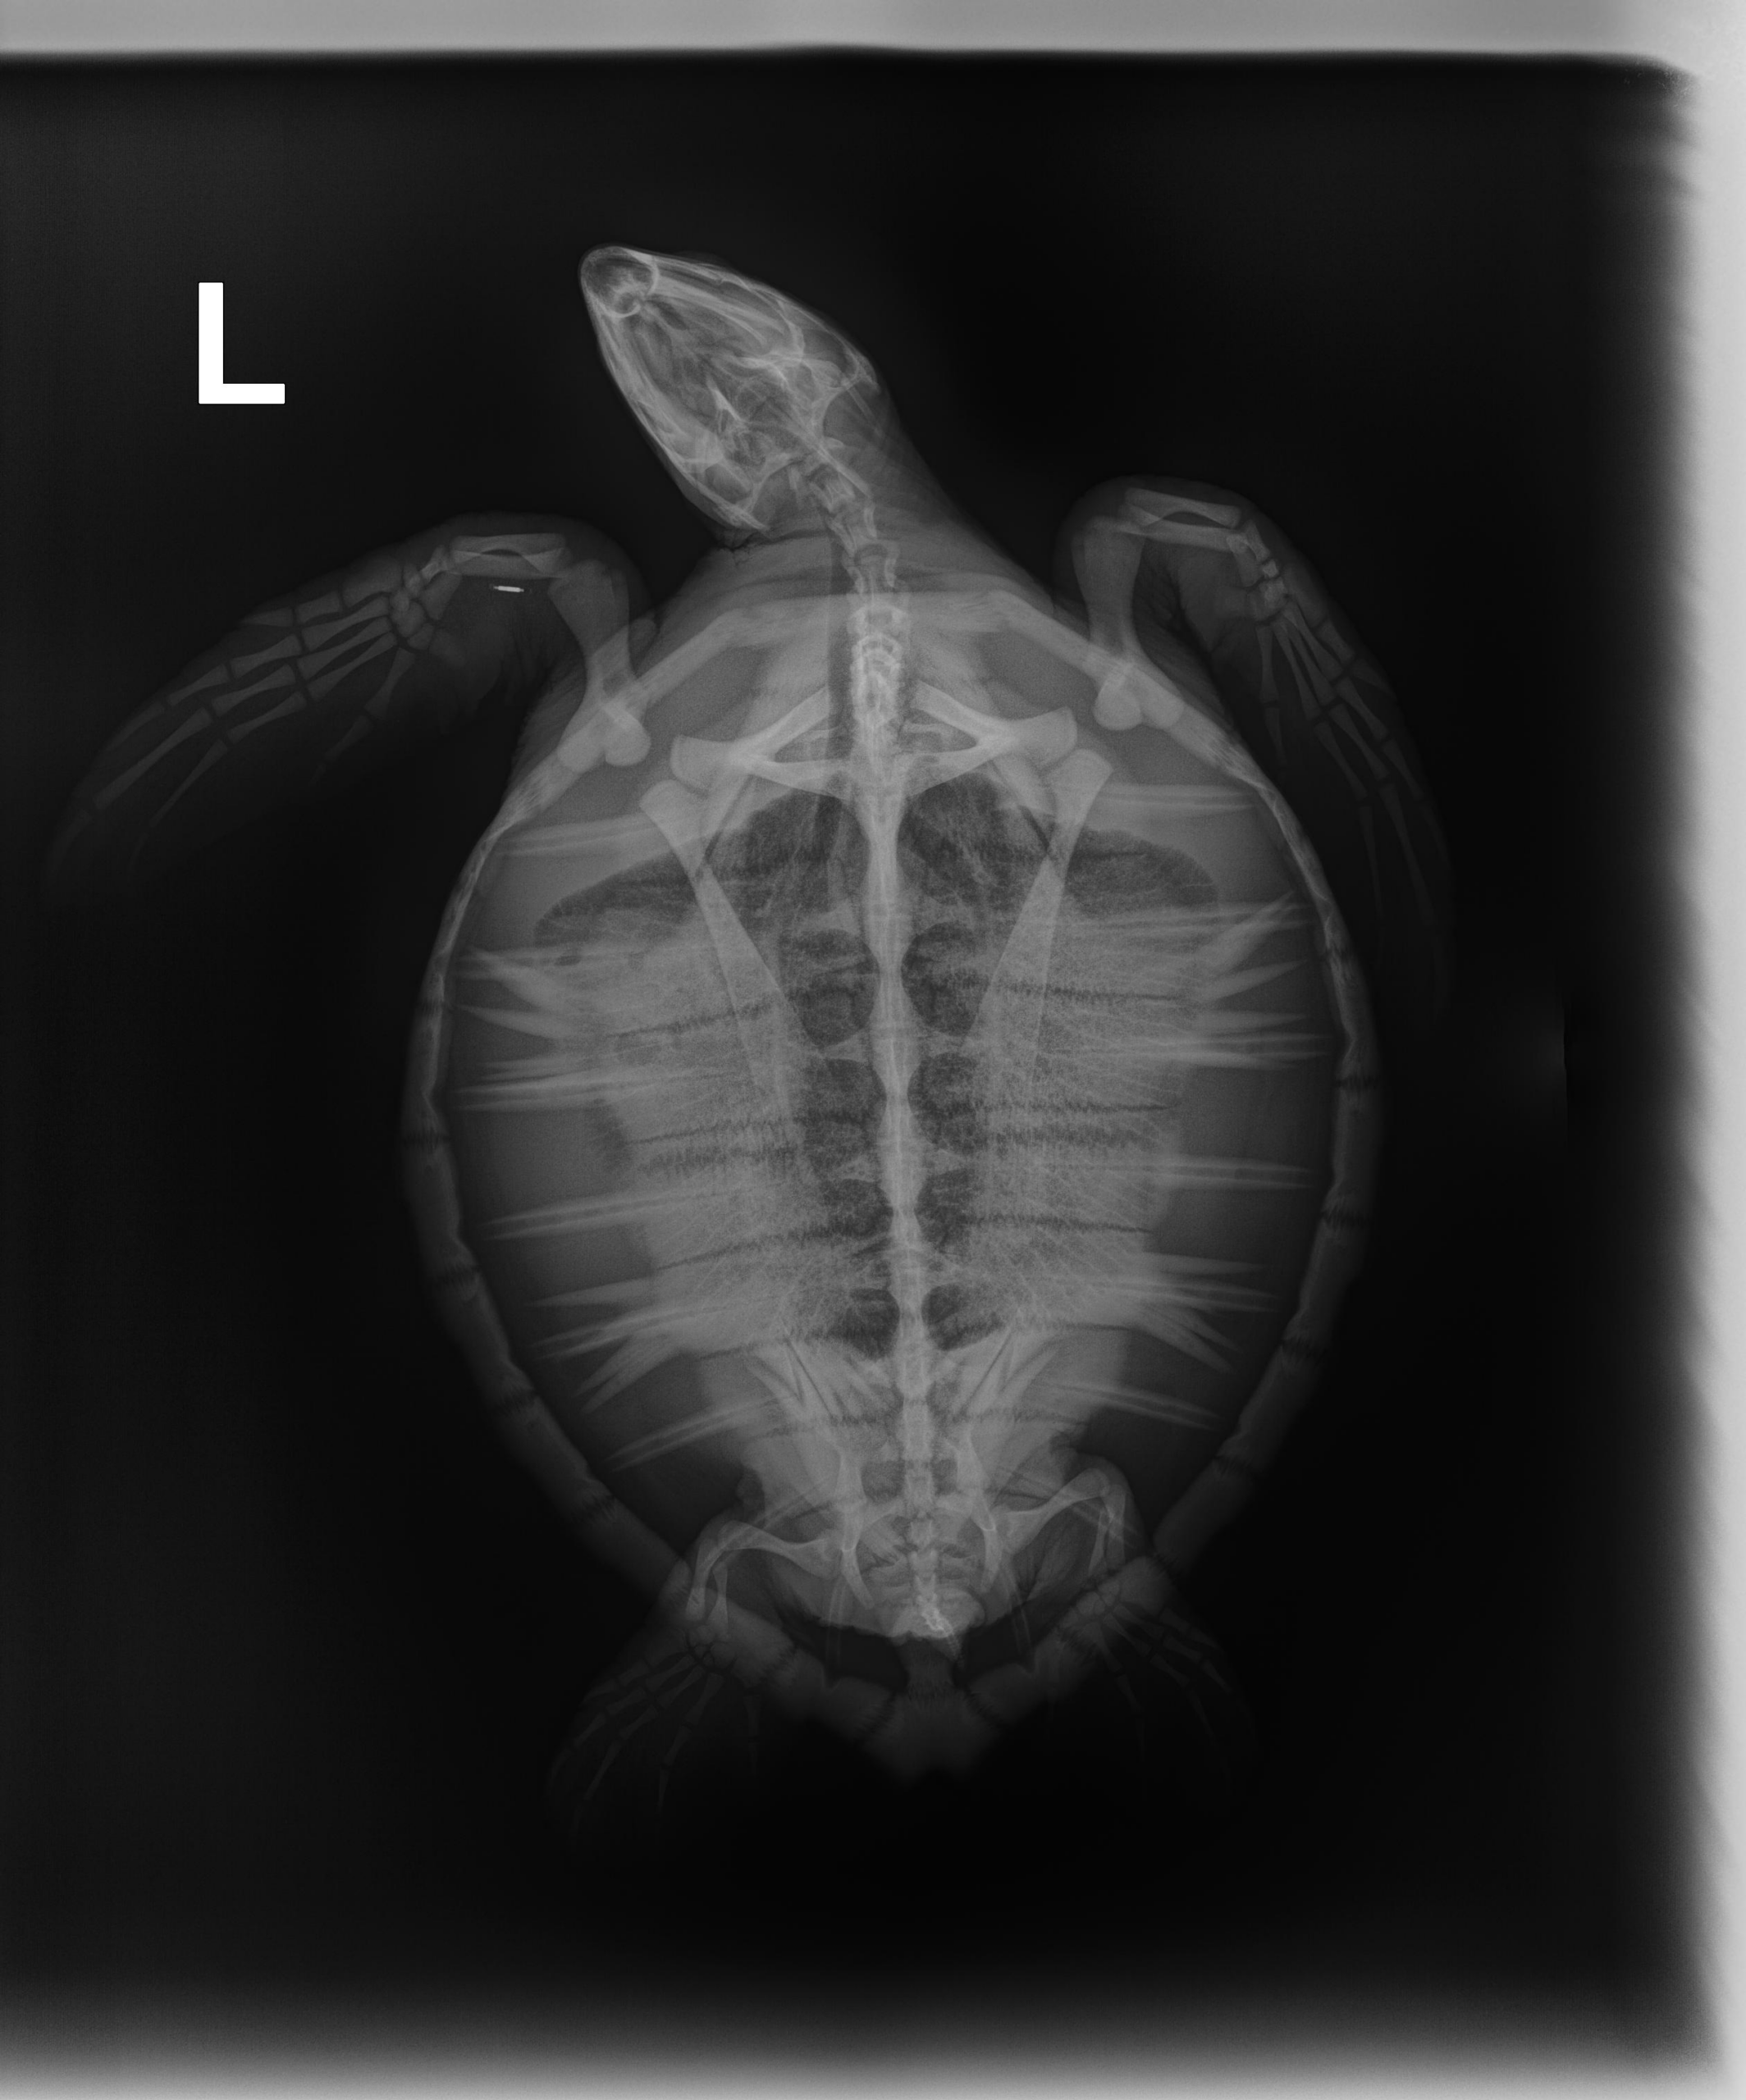

3.6lb non FP juvenile green

Minor abrasion on carapace, moderate abrasions and bruising on plastron, on LFF 2 oozing abrasions and 1 bleeding, 1 bleeding abrasion on right, front flipper. Had a pit tag (can see in dv radiograph).